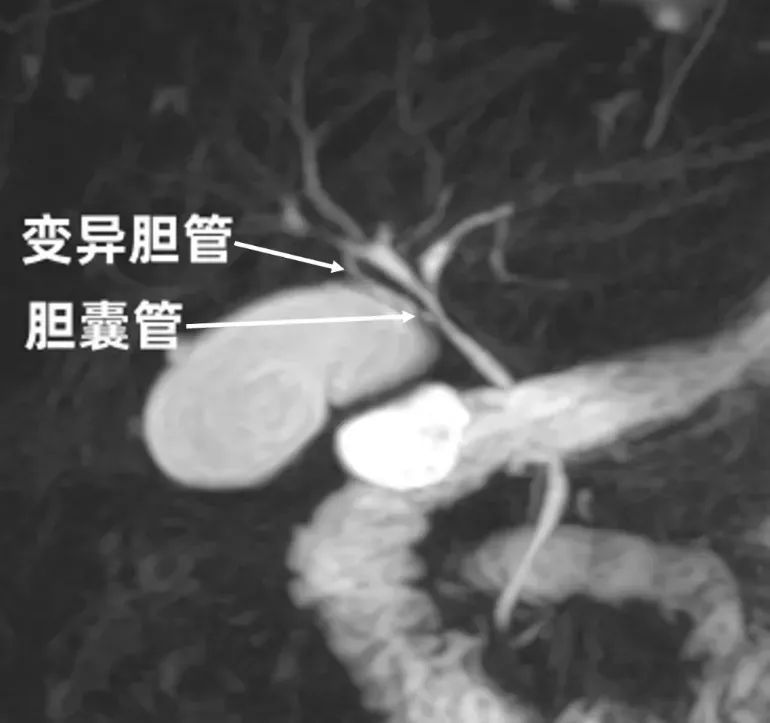

专家团队按常规安排磁共振胰胆管成像(MRCP)检查后意外发现李女士的胆囊有“不同之处”:一根变异的胆管自右后叶胆管发出,通向胆囊,这大大增加了手术的难度。

“如果术中不慎误伤这根‘变异胆管’,可能导致胆汁性腹膜炎、胆瘘,甚至影响肝功能。”外二科张敏峰副主任医师表示。

专家团队基于影像学资料进行了详细分析,决定采用在国内率先提出的“胆囊管浆膜Y形入路”技术,并制定了周密的手术方案。患者在充分了解手术风险和对策后,也同意接受腹腔镜胆囊切除术。